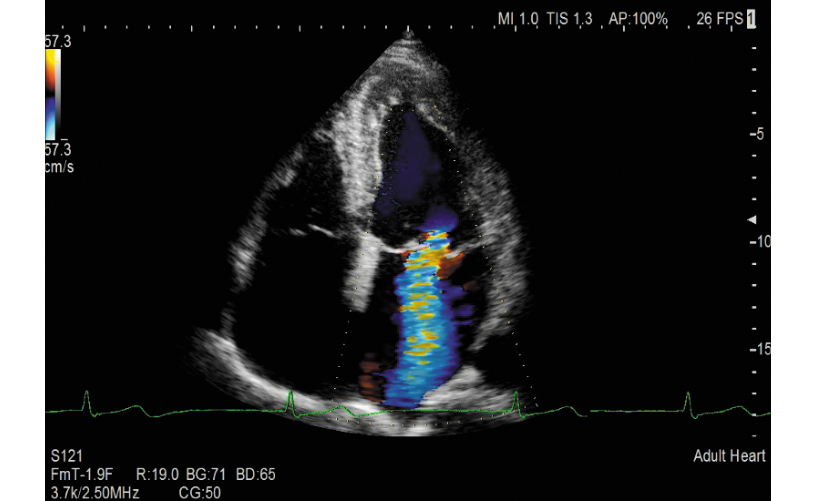

A wide range of essential image adjustment parameters dedicated to high cardiac image quality; a variety of technologies to reduce confounding factors that inhibit signal fidelity such as patient dependent variability; transducers, image processing algorithms, monitor display: PURE SYMPHONIC ARCHITECTURE providing premium level image clarity for cardiac diagnosis.

The phased array transducer has been designed to realize the high spatial, temporal and contrast resolution especially required for cardiology. With an improved shape that is comfortable to hold and fits easily in intercostal spaces, it can reduce variable factors such as user skill- and patient disease-dependencies that can inhibit image clarity.

The transmission/reception technology for LISENDO 880LE realizes significant S/N improvement and reduces focal dependency whilst providing excellent penetration at higher frequencies. eFocusing offers a real-time display not modified by image processing, selected by a one-touch operation.

The Fujifilm Group's image processing technologies evolved from former models are further refined for LISENDO 880LE. Combined with the newly developed transducers and eFocusing technology, they deliver imaging with outstanding definition which can be adjusted for each user's preference.